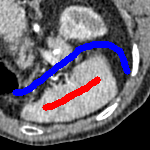

We now introduce two recent methods that incorporate user input to perform selective segmentation. Each involves input in the form of foreground/background regions to indicate relevant structures of interest. An example of this can be seen in Fig. 18, where red regions indicate foreground and blue regions indicate background. We compare against the work of Nguyen et al. Nguyen:12 , which uses a similar convex relaxation framework to the proposed approach, and Dong et al. SRW , which uses a variation of the random walk approach. We summarise the essential aspects of each approach in the following.

Test Images. We will perform initial tests on the images shown in Figs. 5–7. We have provided the ground truth and initialisation used for each image. Test Images 1–3 are synthetic, Test Image 4 is an MRI scan of a knee, Test Images 5–6 are abdominal CT scans, and Test Images 7–9 are lung CT scans. They have been selected to present challenges relevant to the discussion in §2. We focus on medical images as this is the application of most interest to our work. In the following we will discuss the results in terms of synthetic images (1–3) and real images (4–9). We also test the proposed approach on a larger data set of 30 CT images (a sample of which is presented in Fig. 18), comparing against existing selective methods detailed in §3.

In order to further establish the robustness of our method, we now introduce the results of testing our approach against competing interactive segmentation methods on a larger data set. The results are presented in Fig. 17, showing a boxplot of accuracy in terms of TC on a set of 30 CT images (excluding outliers). The target structure we consider is the spleen, as this consists of a relatively homogeneous foreground, appropriate for the approach considered. The data has been manually contoured providing ground truth data for the image set. We compare CAC Nguyen:12 and SRW SRW against our method with five variations of user input for each image. It is worth emphasising here that the input used in the tests is identical for each approach and was not refined in any way. It was designed to mimic what a user, unfamiliar with each approach, might select intuitively. A representative example for three images is shown in Fig. 18. This shows foreground (red) and background (blue) user input regions. For our method, we define the red region as as discussed in §1 and enforce hard constraints on the blue region. We refer to the results of the proposed approach using this input as Ours (i). We also include results of randomising the user input in an identical way to §7.3. For each image we generate 1000 simulated user input choices, which we present as Ours (ii). It is important to note that the difference between Ours (i) and (ii) is only the definition of . The method and parameters are fixed between each.